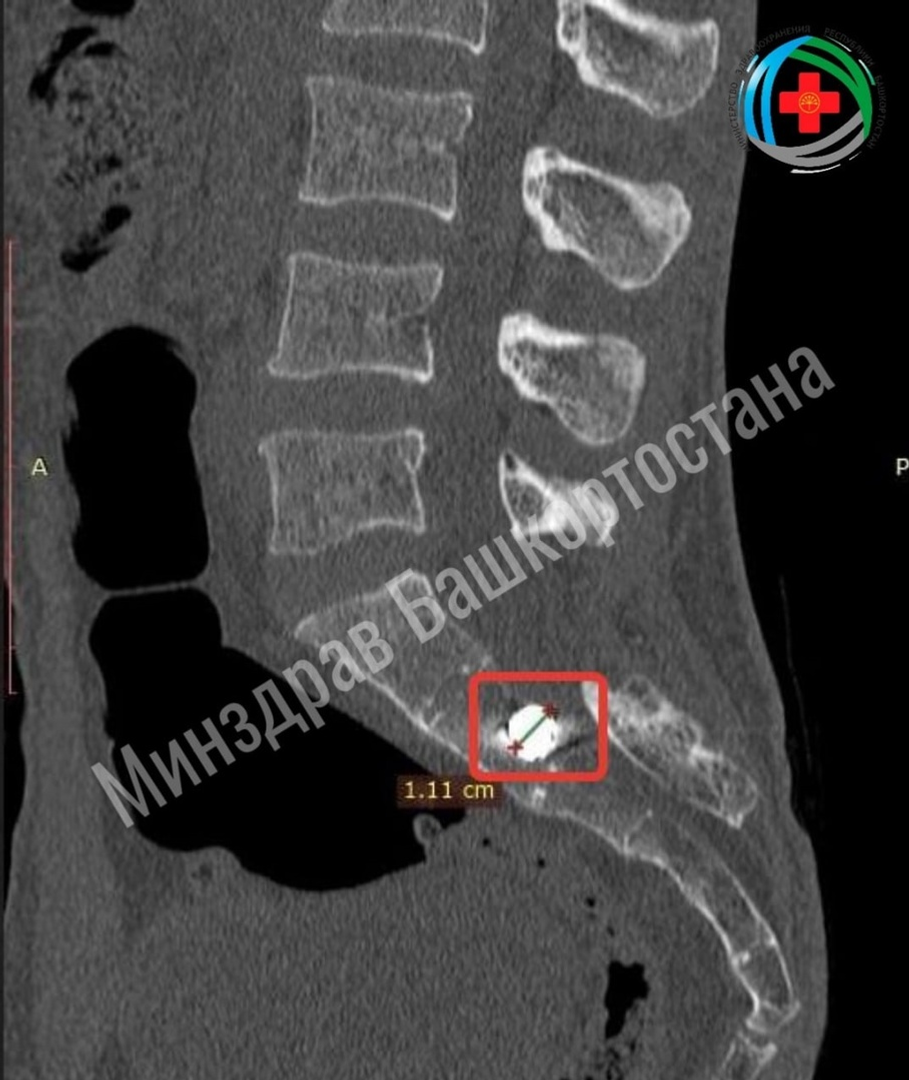

Мужчина получил ранение на поле боя осколком снаряда. Врачи при обследовании выявили, что осколок вошел в область ребер справа, прошел через мягкие ткани, повредив поперечный отросток пятого поясничного позвонка, и раздробил задние отделы крестца. Он также пробил спинной мозг и застрял в кости.

Врачи успешно удалили осколок кубической формы размером один сантиметр — они аккуратно обошли спинной мозг, не повредив его, а пациент уже тем же вечером смог встать на ноги. Послеоперационная рана зажила без проблем, бойца выписали для дальнейшего реабилитационного лечения.